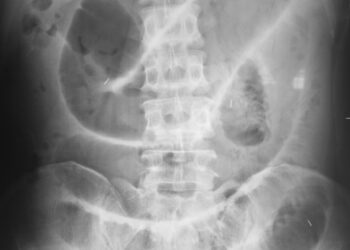

Skaityti daugiauDetailsMegaureteris – tai būklė, kai vienas ar abu šlapimtakiai tampa neįprastai platūs. Šlapimtakis yra siaura, apie 9 centimetrų ilgio ir...